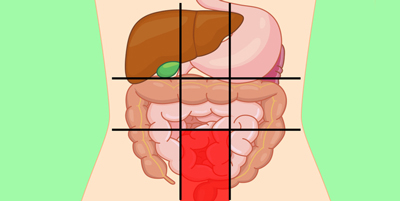

عکس داخل شکم انسان. در این همان طور که مشخص است شکم حالت بیضی شکل پیداکرده و این بیضی که کناره های شکم کشیده شده است. تعداد سلول های بدن انسان حدود ۳۷ ۲ تریلیون تخمین زده شده اند. Abdomen که در زبان عامه به غلط به آن دل نیز می گویند در آناتومی به قسمتی از تنه گفته می شود که مابین دیافراگم از بالا و سطح فوقانی لگن خاصره از پایین قرار دارد. ربات دیدنی ربات انساننمای چینی به صورت یک دختر جوان ساخته شده و جیا جیا نامگذاری شده است این ربات طوری برنامهریزی شده که میتواند صحبت کند و احساسات خود را از طریق تغییرات در چهره حالات.

شکل دوم شکم مادری را نشان می دهد که جنین دختر دارد. وحشت مادر از عکس سونوگرافی جنین داخل شکمش عکس. تصاویر جالب از داخل مغز و نخاع انسان آخرین نیوز. بدن انسان کل ساختار انسان است که سر گردن تنه سینه و شکم دو بازو و دست ها و دو ساق پا و پاها را شامل می شود.